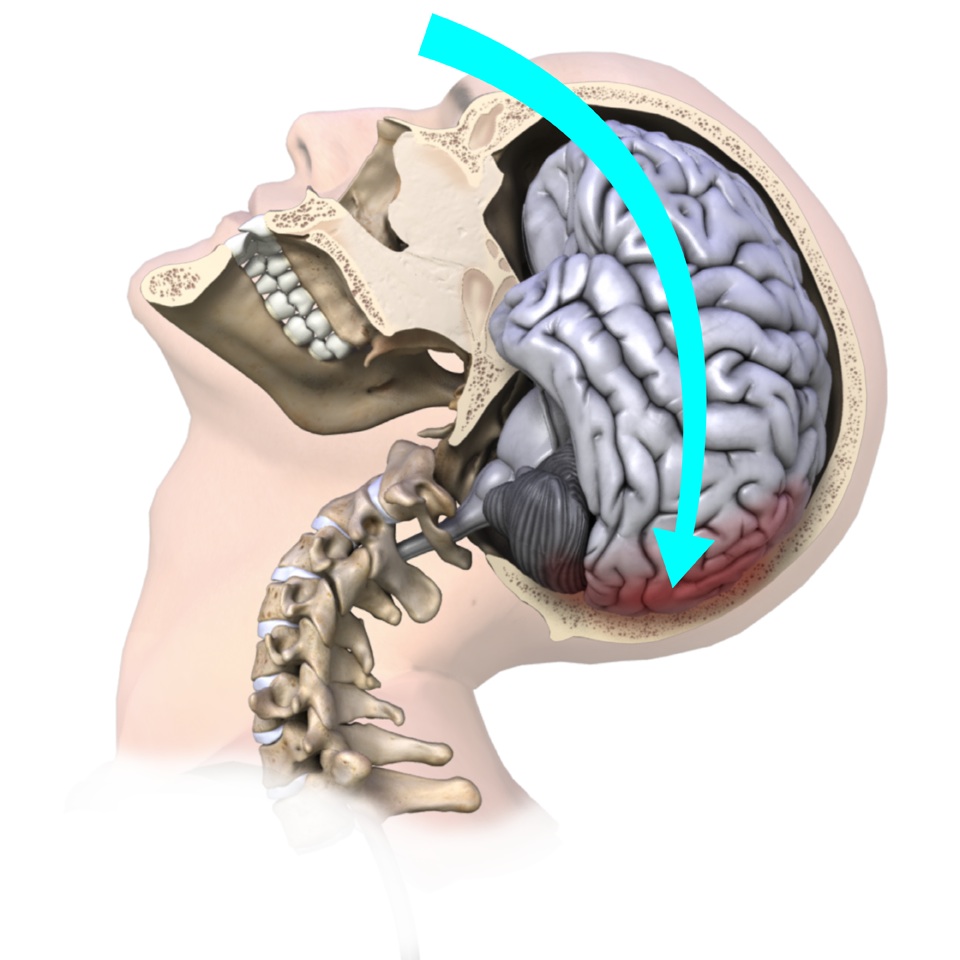

The brain is a soft organ that sits in the hard skull for protection. It is cushioned by cerebrospinal fluid that fills in the space between the skull and the brain. The cerebrospinal fluid acts like packing foam that protects your fragile items from both the sides of the hard moving box itself and from the rapid or sudden motions that the box may endure.

Any forc e that causes the brain to move rapidly within the skull and bang against the inside of the skull can cause a concussion. In layman’s terms, a concussion can be caused by anything that ‘rattles the brain.’

Typically concussions are thought to be caused by direct blows to the head, such as in boxing or bar fighting, or by hitting your head on the ground during a fall, but indirect forces to the head are also common causes of concussions. For example, a fall onto your buttocks or onto any other part of your body can transmit a force strong enough to your brain to cause a concussion, even if you do not hit your head during the fall. Similarly, a blow to your neck, face or any other area of your body that is severe enough to transmit the force to your head can cause a concussion.

Motor vehicle accide nts often similarly cause concussions due to the whiplash motion of your neck which subsequently forces your brain to rapidly hit the inside of your skull. Shaken baby syndrome is another example of this indirect mechanism of brain injury, as are explosions where your body is rapidly thrown back.